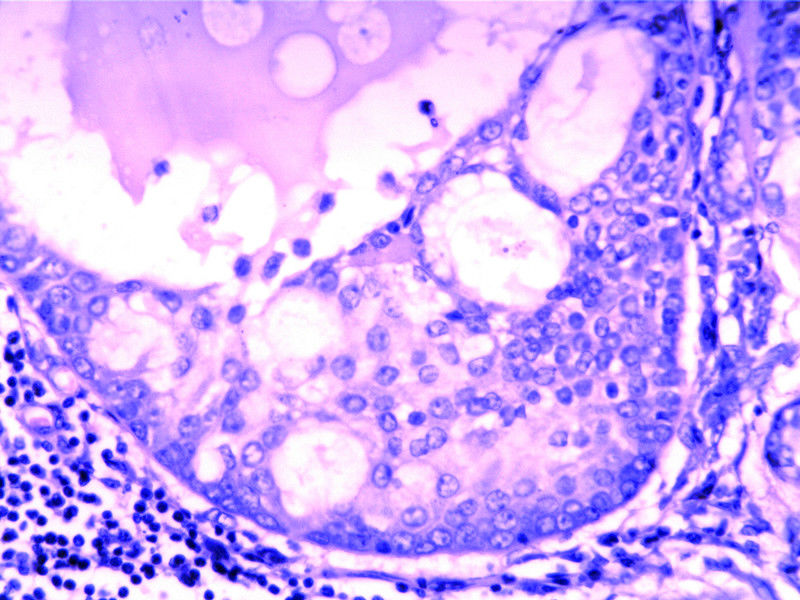

要想Hold住这个肿物的病理诊断,需要了解:

需要鉴别的肿瘤:

(1)皮脂腺淋巴腺瘤

(2)伴有淋巴组织间质的皮脂腺癌(皮脂腺淋巴腺癌)

(3)良性淋巴上皮病

(4)粘膜相关淋巴组织淋巴瘤(MALT淋巴瘤)

(5)转移性粘液表皮样癌